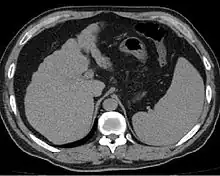

Other scans include CT of the abdomen and MRI.[45] A CT scan is non-invasive and may be helpful in the diagnosis.[45] Compared to the ultrasound, CT scans tend to be more expensive. MRI provides excellent evaluation; however, is a high expense.[45]